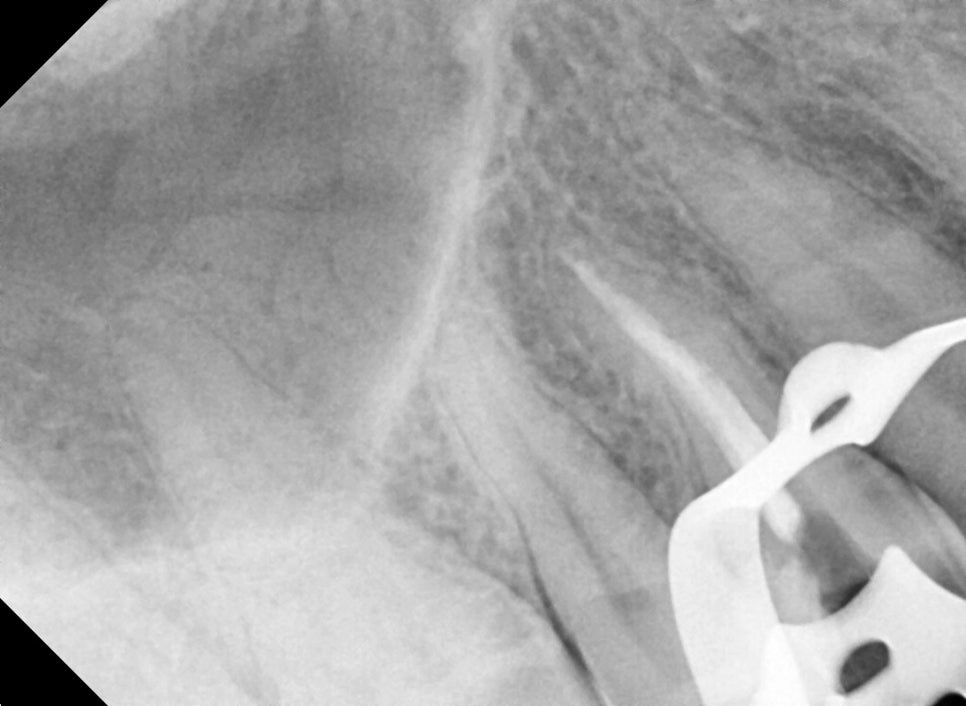

왼쪽 사진: 신경치료 중 촬영한 X-ray 사진입니다. 근관(치아 뿌리) 내부까지 약물이 잘 도달했는지 확인하는 과정입니다.